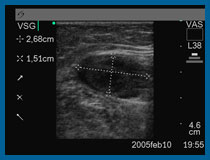

A nivel vascular, el Eco-Doppler color se utiliza, para “ver” en directo, con el Eco los vasos sanguíneos, su calibre, su estructura, y las modificaciones en sus paredes.

Con el Doppler y Doppler Color, medimos la velocidad de flujo, e indirectamente el volumen circulante en un determinado vaso ( arteria o vena) .

A nivel de venas varicosas, nos permite hacer un “mapeo” de todas ellas a lo largo de la extremidad, observando la disposición superficial o profunda y permitiendo localizar los puntos de reflujo desde el sistema venoso superficial al profundo.

A nivel de arterias, podemos estudiar especialmente las consecuencias de la arterioesclerosis, u otras enfermedades arteriales, observando la deformación de las paredes arteriales, la presencia de placas ateromatosas, y midiendo el flujo o volumen de sangre circulante de una determinada arteria a un determinado nivel. Se estudian especialmente los llamados troncos supraórticos (arterias carótidas, subclavias y vertebrales) y las arterias de las extremidades superiores o inferiores. Igualmente la aorta torácica y abdominal arterias ilíacas, arterias renales etc.